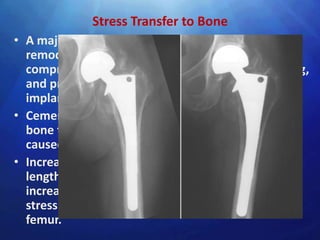

Stress Transfer to Bone

• A major concern with THR is that adaptive bone

remodeling arising from stress shielding

compromises implant support, produces loosening,

and predisposes to fracture of the femur or the

implant itself.

• Cementless stems generally produce strains in the

bone that are more physiological than the strains

caused by fully cemented stems

• Increasing the modulus of elasticity, the stem

length, and the cross-sectional area of the stem

increases the stress in the stem, but decreases the

stress in the cement and proximal third of the

femur.